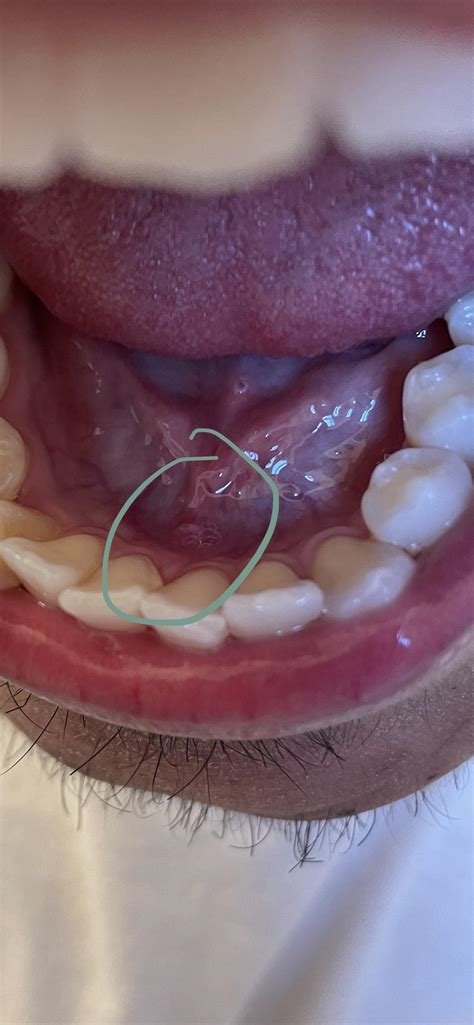

Oral skin tags, also known as fibromas or acrochordons, are small, benign growths that can appear on the skin inside the mouth. These growths are typically flesh-colored or slightly darker and can vary in size from a few millimeters to several centimeters. While oral skin tags are generally harmless, they can sometimes cause discomfort or interfere with daily activities such as eating or speaking. Understanding the causes, symptoms, and treatment options for oral skin tags is essential for managing this condition effectively.

Oral skin tags are soft, non-cancerous growths that develop on the mucous membranes inside the mouth. They are composed of loose collagen fibers and blood vessels covered by skin. These tags can appear on the lips, tongue, cheeks, or gums and are usually painless. However, they can become irritated or inflamed if they are repeatedly rubbed or bitten.